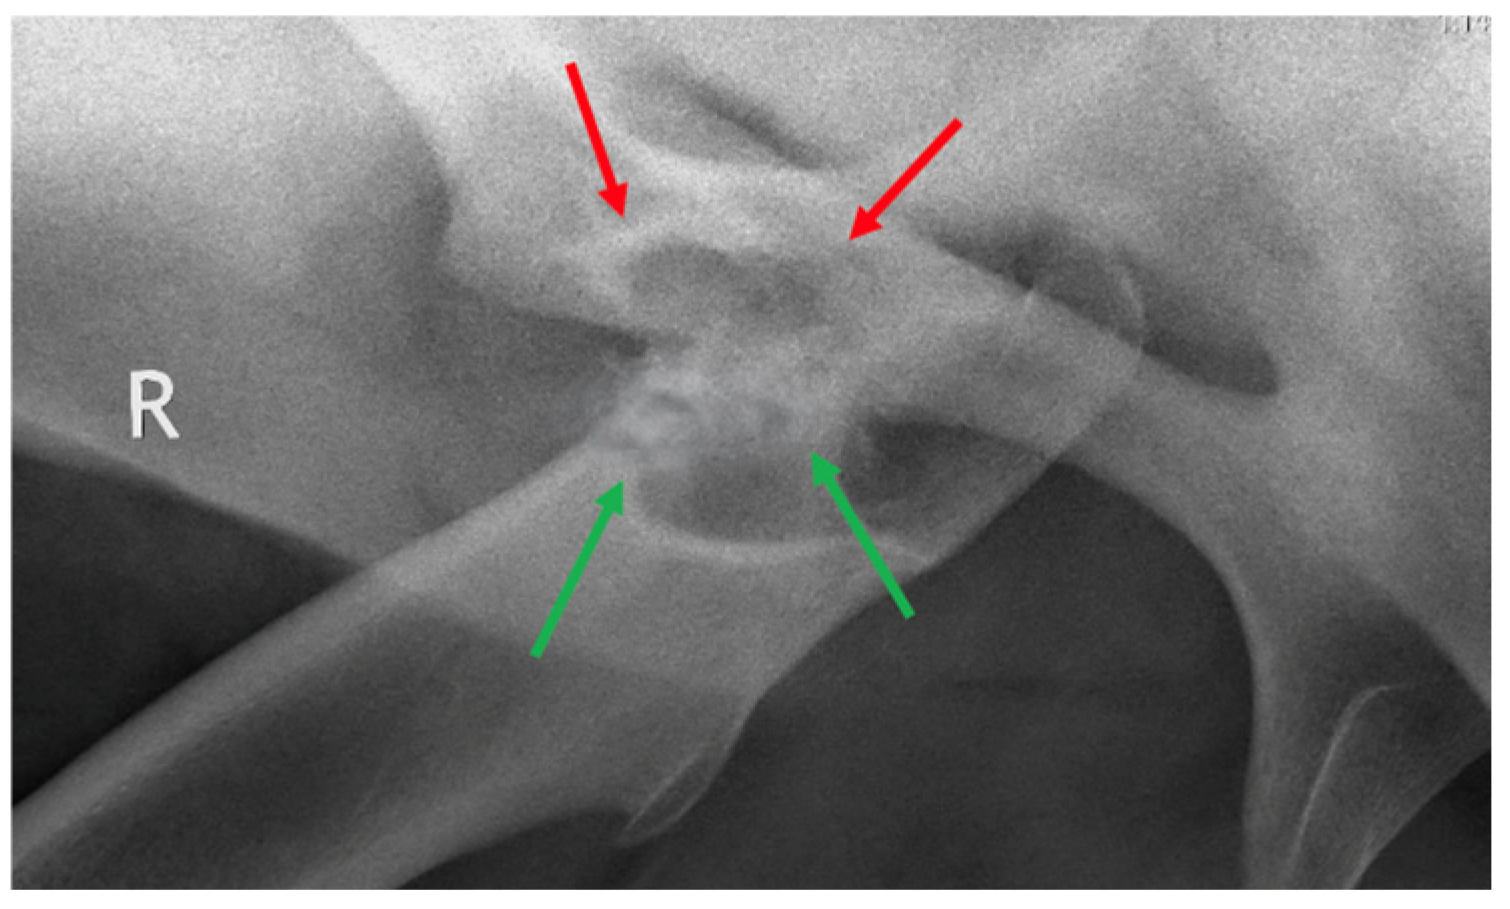

2.2. Diagnostic Imaging